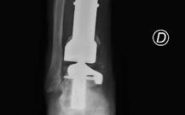

Alla diagnosi è seguita la resezione del tumore con impianto di una mega-protesi di tibia prossimale, cioè nell'area vicino al ginocchio. Dopo circa un anno dall'intervento, però, una grave infezione della protesi impiantata ha costretto Mario a subire una serie di complessi interventi chirurgici che si sono conclusi con l'impianto di una protesi totale di gamba e di caviglia in titanio, rivestita in argento per evitare nuove infezioni.

Una gamba bionica.

Ma ancora non era finita. A distanza di 6 anni, Mario torna dagli ortopedici del Gemelli per un dolore alla caviglia. Gli esami rilevano la rottura di una vite della protesi, a livello della caviglia. E' necessario sostituire il pezzo, ma l'unico modo per farlo – decretano gli specialisti – è facendo confezionare una protesi 'custom-made', disegnata e realizzata su misura. Gli ortopedici del Gemelli inviano perciò la Tac di Mario all'Implantcast, una ditta specializzata di Buxtehude, cittadina a sud ovest di Amburgo, in Germania. Basandosi sulla ricostruzione tridimensionale della caviglia bionica di Mario, i bioingegneri realizzano un calco della protesi custom-made con una stampante 3D, sul quale viene realizzata la protesi in titanio per l'impianto definitivo. Ed ecco l'intervento effettuato da Carlo Perisano, professore aggregato dell'Università Cattolica del Sacro Cuore e dirigente medico presso la Uoc di Ortopedia e Traumatologia della Fondazione Policlinico Gemelli, diretta da Giulio Maccauro. L'operazione dà i suoi frutti: "A distanza di appena qualche giorno dall'intervento, Mario sta di nuovo in piedi sulla sua gamba bionica arricchita di quest'ultimo gioiello tecnologico", riferiscono dall'Irccs capitolino. (segue)